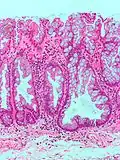

| Tubular Adenoma (Villous, Tubulovillous) | Colorectal | Tubular glands with elongated nuclei (at least low-grade atypia) | Yes | ![]() |

|